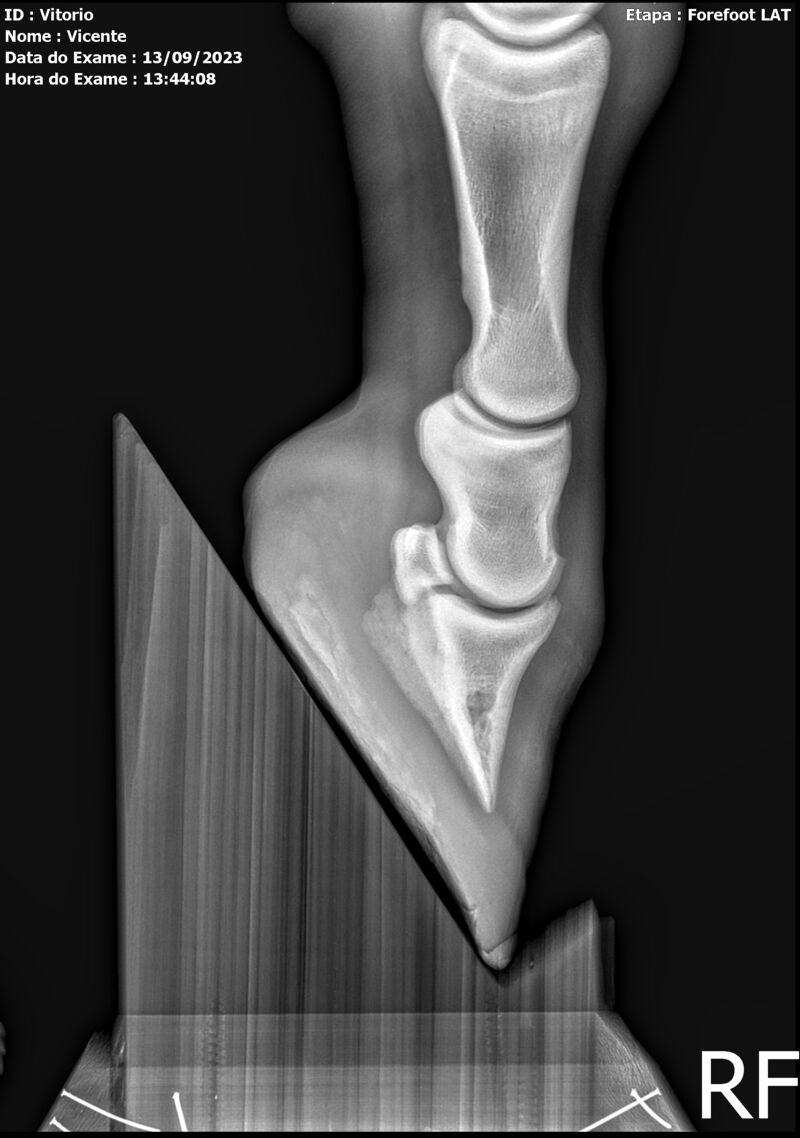

THUNDER ZC

Raça: BRASILEIRO DE HIPISMO

Sexo: MACHO - POTRO

Nascimento: 17/09/2022

Altura Aproximada: 1,54

Pel.: CASTANHO

Registro: EM AND

Vend.: VICENTE CONTE

Local : PORTO FELIZ/SP